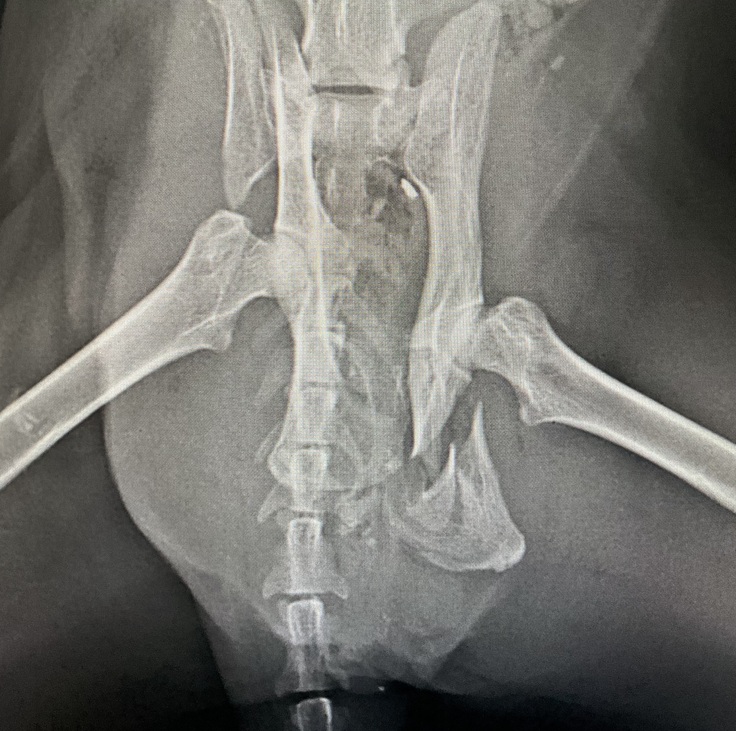

・骨盤骨折

骨盤骨折の手術を実施。

◆10月17日

◆10月29日

退院(抜糸済)

診断結果から、今後も腎臓や口腔の治療が必要になる見込みです。